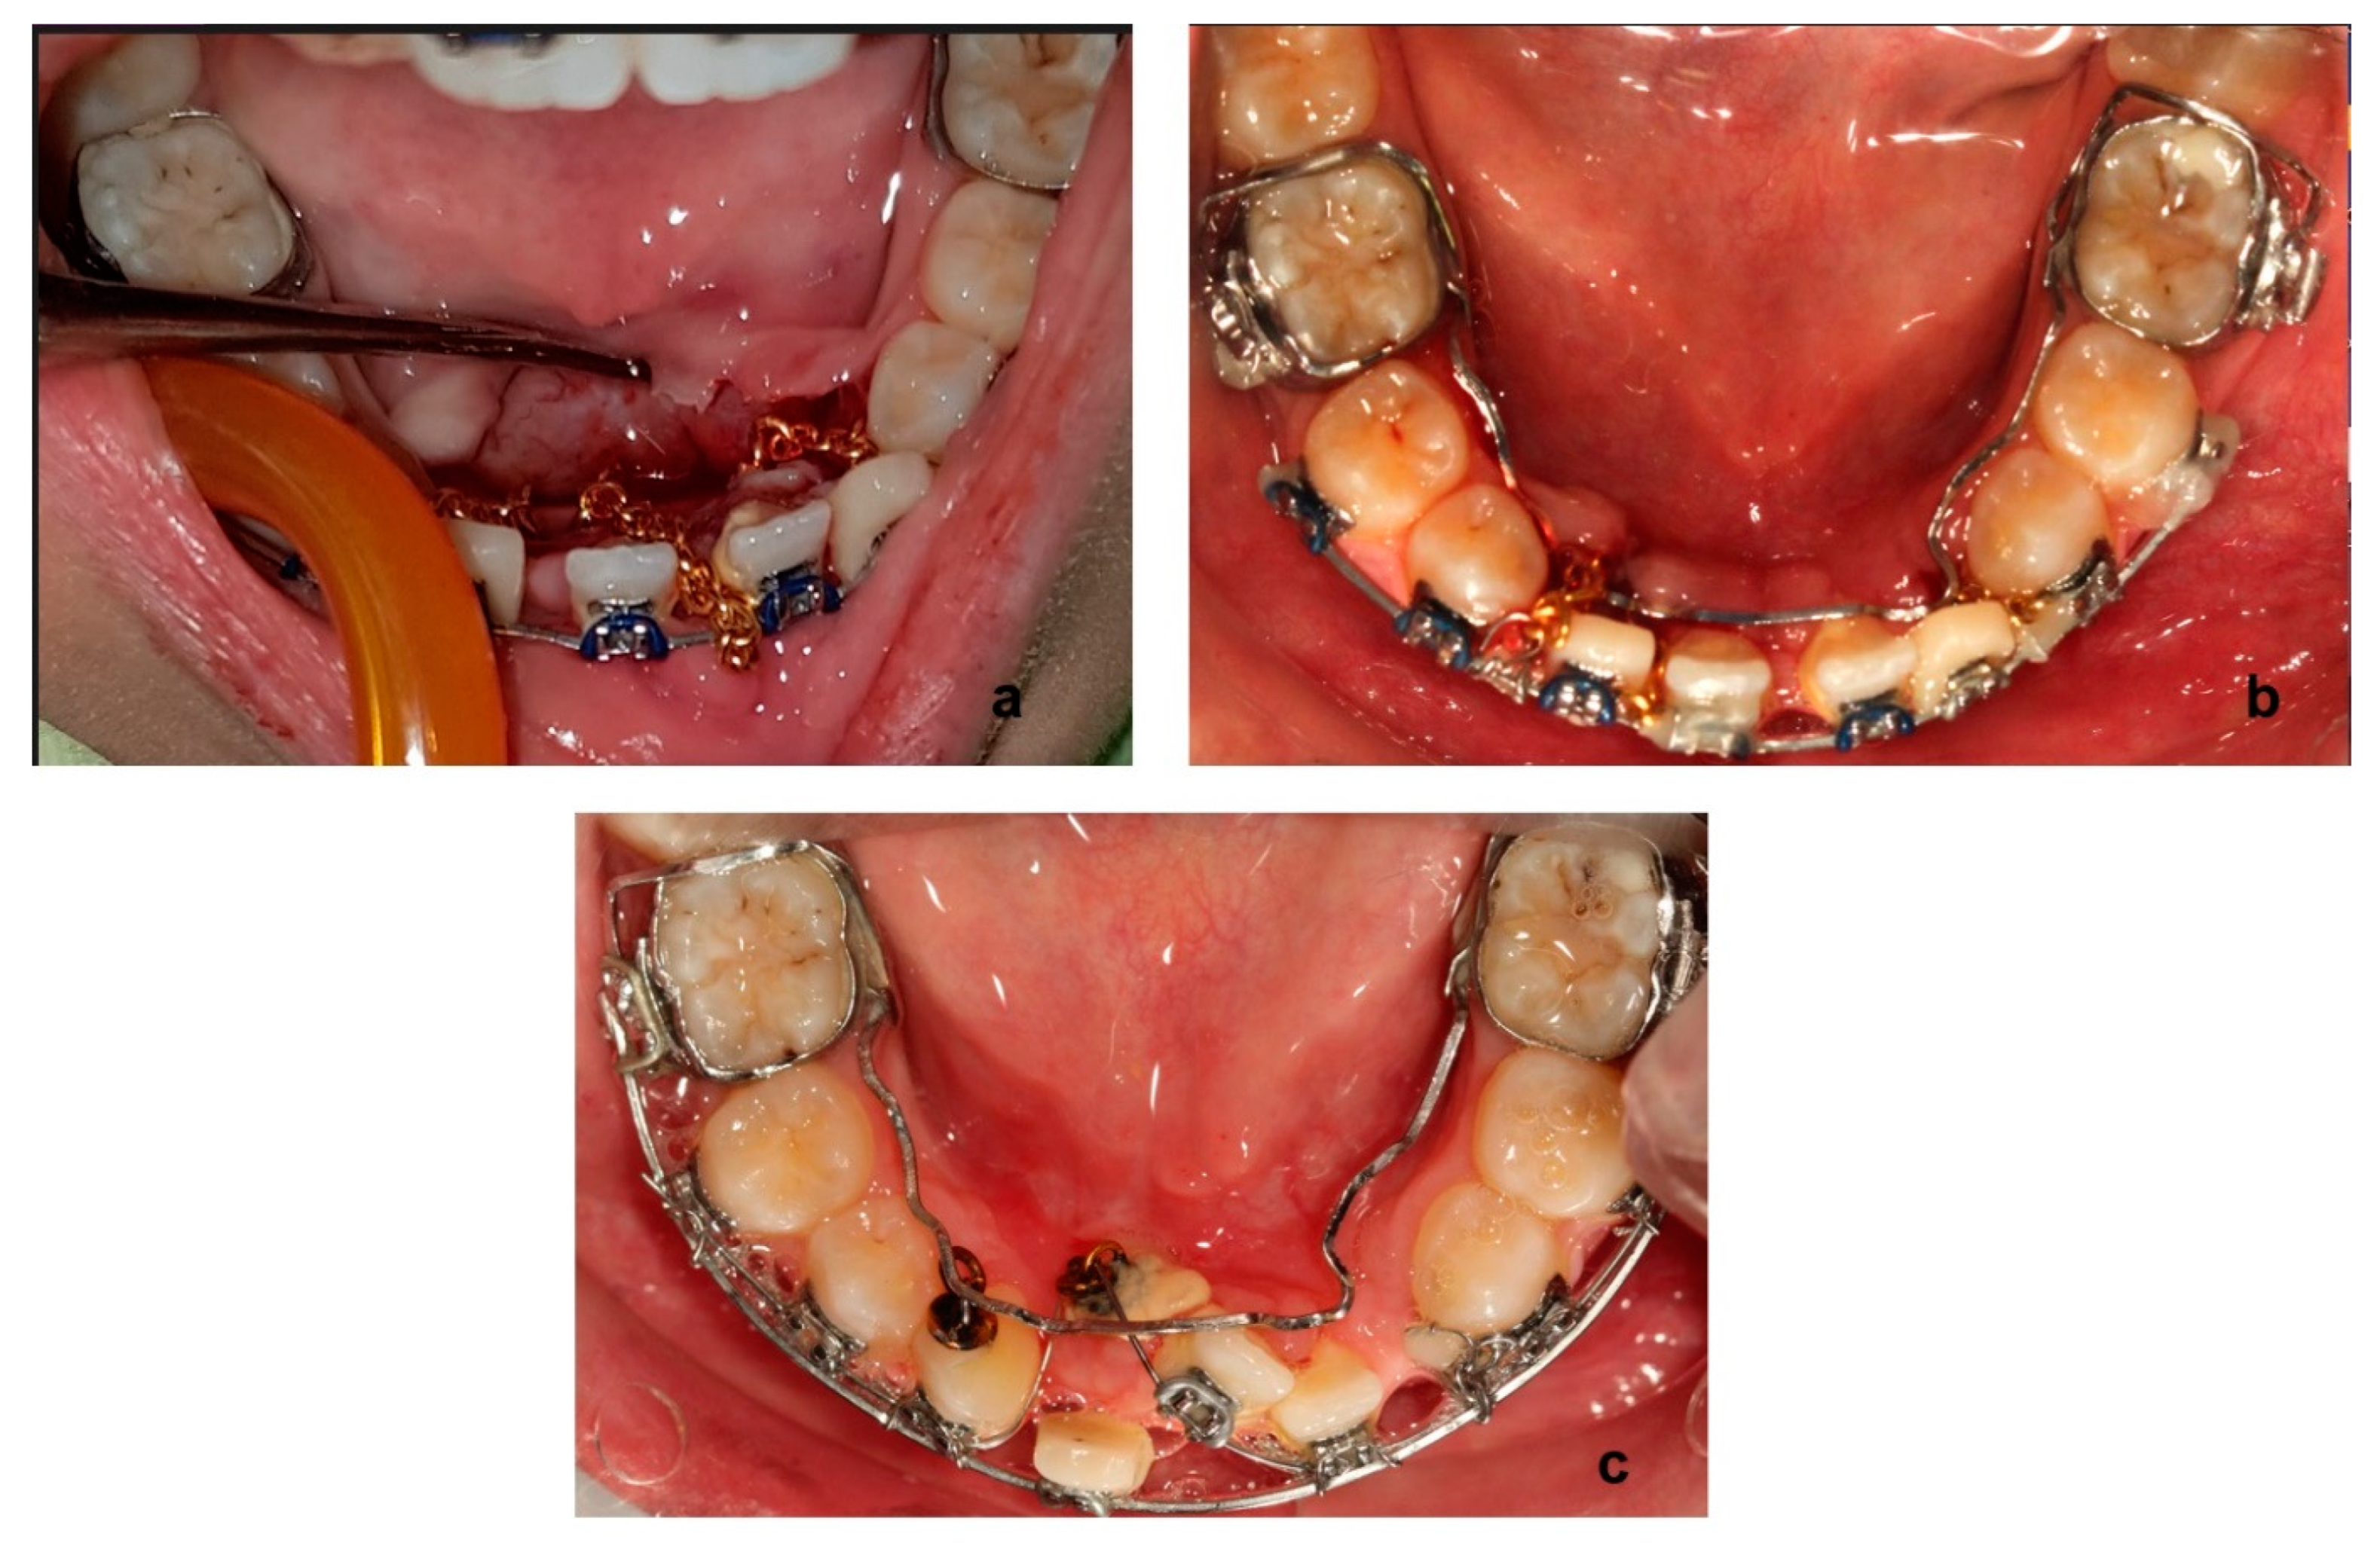

The closed eruption technique was chosen. Lower canines and the two incisors were surgically exposed, and a gold chain apparatus was bonded on each one (Figure 7a). A 0.17 × 0.25 SS wire, leaning on the buccal tubes of the lower molar bands, was properly fitted around them and on the lingual side of the lower teeth crown (Figure 7b). This was chosen in order to suspend (in conjunction with the labial brackets and wires) either an elastic chain or a super-elastic wire from the certain wire in order to facilitate traction of the impacted teeth (Figure 7c). This was performed for 43, 42, 32, and 33 separately one after the other, in that order.

Figure 7. Intraoral photos from surgical exposure (a) and traction (b,c) of the impacted teeth.